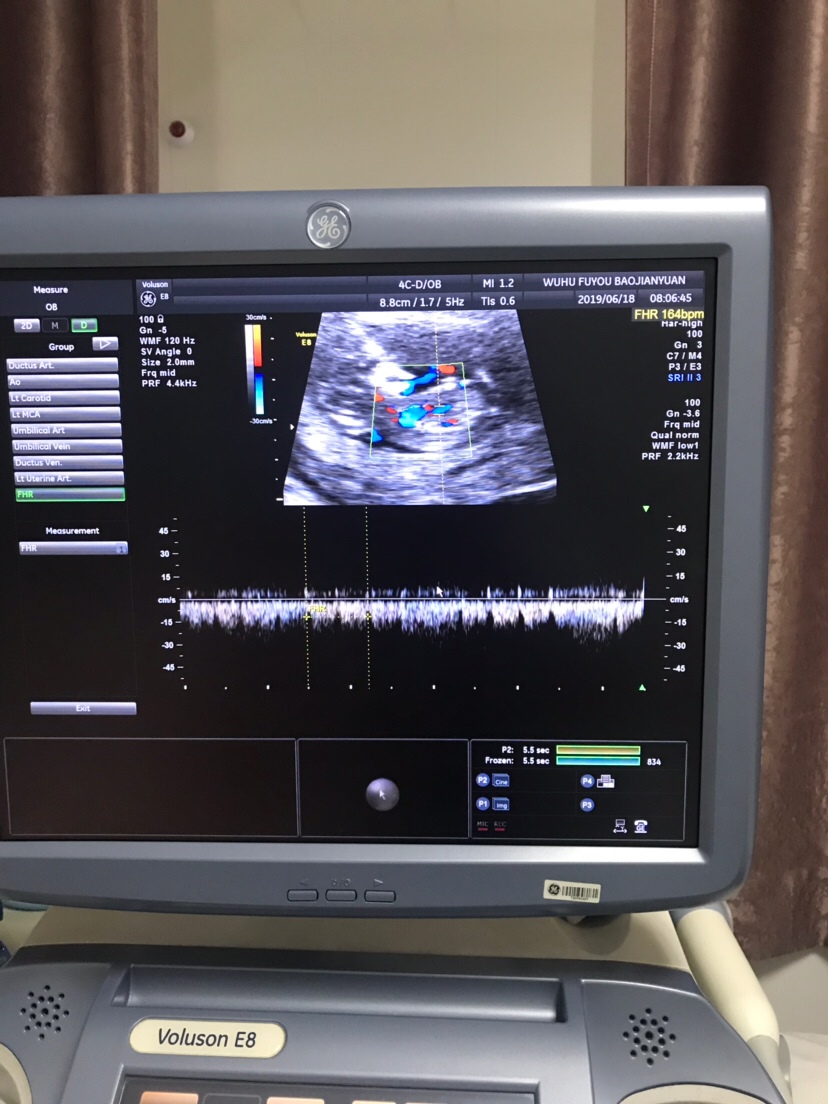

可乐双胞胎兄弟

2018-06-01

2736 人回复